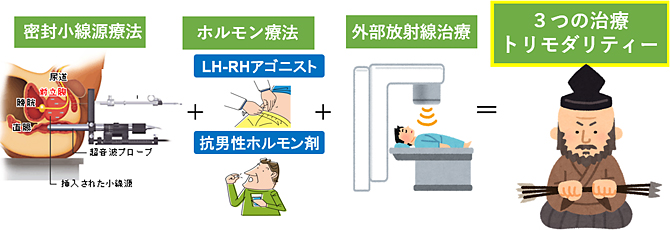

トリモダリティ療法とは?

3つの治療を組み合わせた、高リスクに効果的な治療法です。前立腺とその周囲により強い放射線を照射でき、さらにホルモン療法の相加・相乗作用と微小転移への治療が加わり、高い生化学的非再発率が得られます。